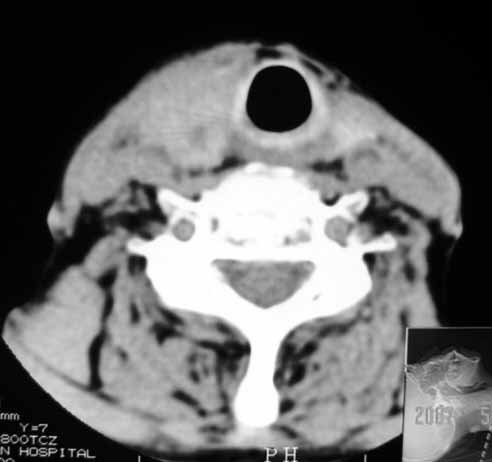

以下是引用jw-830在2007-5-24 15:33:00的发言:[br]右侧甲状腺增大,内可见低密度,病灶与周围软组织界线欠清晰,建议增强扫描除外甲状腺癌

以下是引用adams在2007-5-24 17:15:00的发言:[br]支持“ 右侧甲状腺增大,内可见低密度,病灶与周围软组织界线欠清晰,建议增强扫描除外甲状腺癌”。 [br] [br] [br][br] [br] [br]

以下是引用苯小孩在2007-5-24 15:26:00的发言:[br]左侧甲状腺腺癌或瘤,建议穿刺或核素进一步检查.